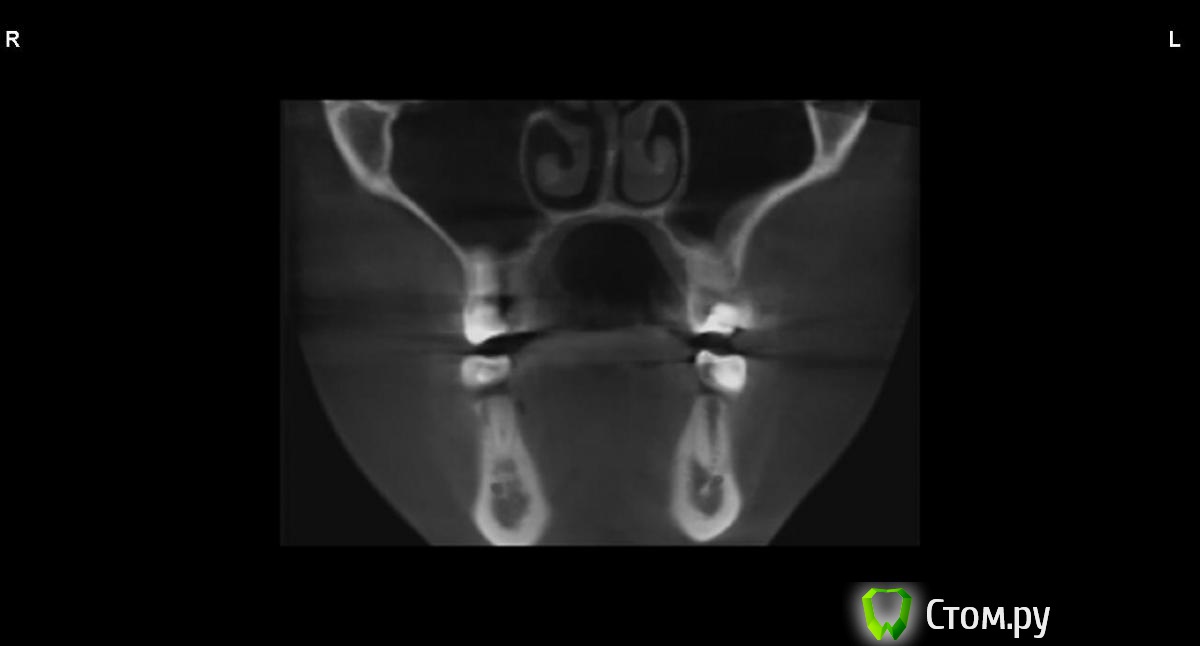

jm3300 Опубликовано 9 сентября, 2014 Автор Поделиться Опубликовано 9 сентября, 2014 в области 25,26 Ссылка на комментарий

jm3300 Опубликовано 9 сентября, 2014 Автор Поделиться Опубликовано 9 сентября, 2014 вот, набросал Ссылка на комментарий

АнтонТЛТ Опубликовано 9 сентября, 2014 Поделиться Опубликовано 9 сентября, 2014 (изменено) это нижняя носовая раковина, возможно Изменено 9 сентября, 2014 пользователем АнтонТЛТ Ссылка на комментарий

АнтонТЛТ Опубликовано 9 сентября, 2014 Поделиться Опубликовано 9 сентября, 2014 я понял что это)))это артефакт от зуба, обратите внимание на правую сторону, там в пазухе тоже зуб есть, после эндодонтии)) Ссылка на комментарий